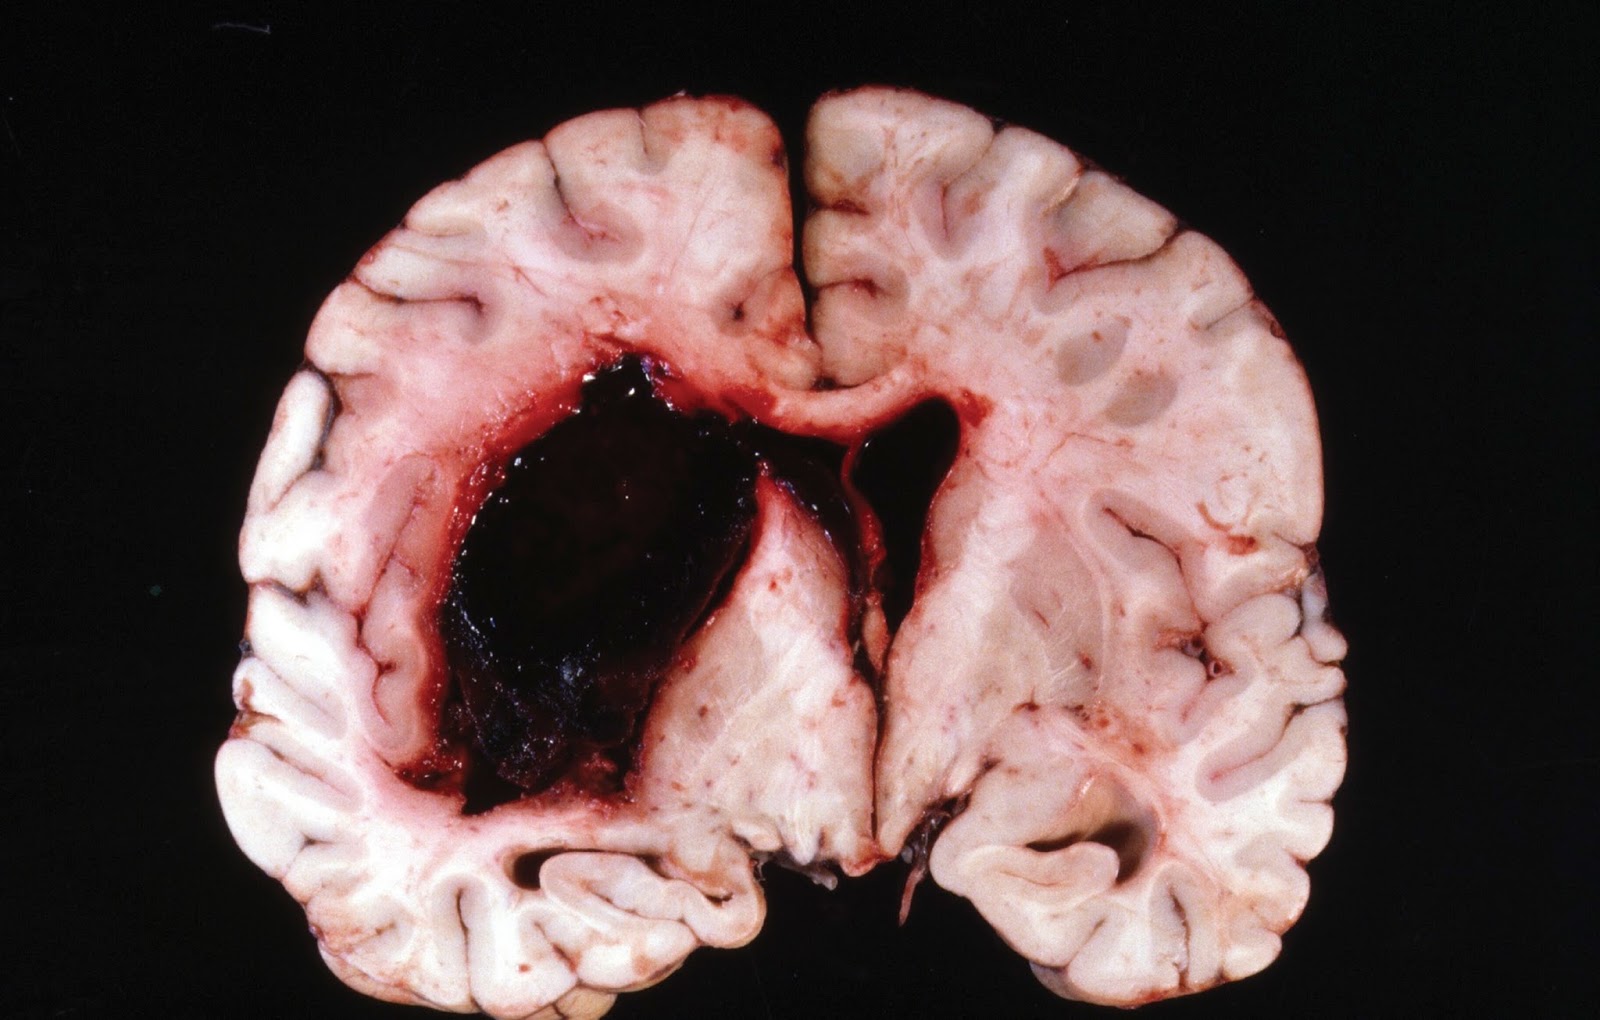

Среди распространенных патологий можно выделить субарахноидальное кровоизлияние в головной мозг, которое возникает по причине…